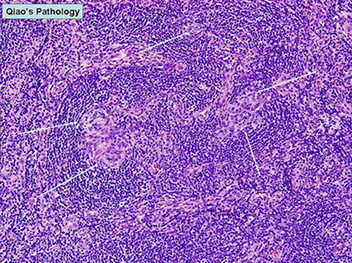

Kikuchi-Fujimoto disease [3] - Classic low-power appearance with reactive follicles at the periphery and paracortical expansion.

Kikuchi-Fujimoto disease [3]

Maturation of necrotizing process in KFD

Kikuchi-Fujimoto disease [3] - histiocytes can have a crescent forms (bottom middle), or xanthomatous forms (bottom left) in later (cleanup) phases, immunoblasts with prominent nucleoli and vesicular chromatin (bottom right), and plasmacytoid dendritic cells (top middle) which are CD123+, and necrosis (top left)

KFD with characteristic necrosis, crescentic histiocytes, clusters of PDCs, and MPO staining in histiocytes